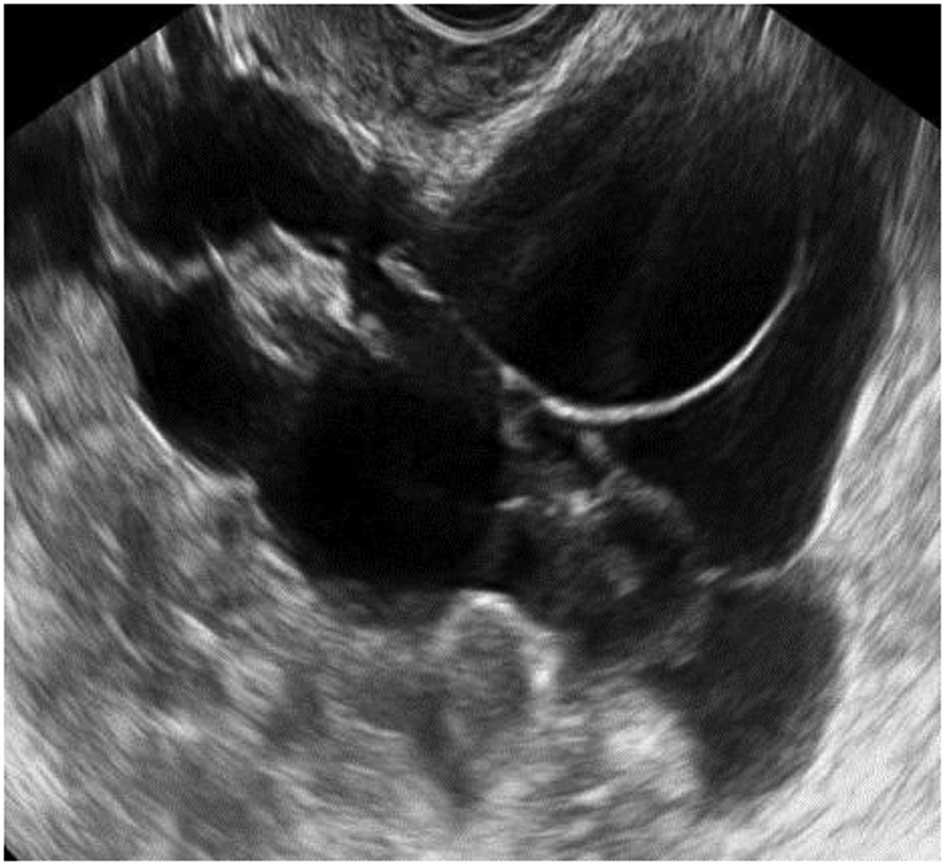

Endometriomas

Ultrasonography is particularly sensitive for accurately diagnosing ‘typical’ endometriomas, most commonly seen in premenopausal women. Typically an endometrioma is a unilocular tumor and has low-level echogenicity representing old blood in the cyst cavity (commonly termed ‘ground glass’). It is this ‘ground glass’ feature that is the most typical feature (28,31–33) (Fig. 15).

Figure 15

Typical endometriomas.

Endometriomas may also have atypical features, and frequently debris within the cyst may give the impression that it is a unilocular-solid lesion with solid papillary projections. In postmenopausal women the appearances of an atypical endometrioma should be examined very carefully as there is a significant risk of malignancy in such lesions in this age group (29,32) (Fig. 16).

Figure 16

Atypical endometriomas with solid papillary projections. (A) Multilocular solid endometrioma. (B) Unilocular solid endometrioma.

During pregnancy endometriomas can change their appearance secondary to decidualization. The features may become quite alarming, with solid vascular projections into the cyst cavity. When no pre-existing scan of the ovary is documented it is difficult in these cases not to suspect malignancy (Fig. 17), although papillary projections were a more frequent sonographic feature among malignant lesions than among benign endometrioid cysts (34,35).

Figure 17

Decidualized endometrioma in pregnancy with vascularized papillary projections.